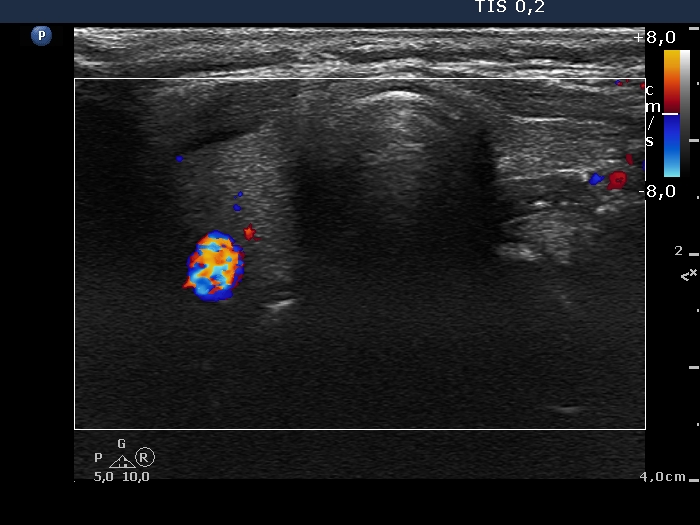

First examination (first row of images):

Clinical data: A 22-year-old woman came to a follow-up examination. She has been diagnosed with euthyroid Hashimoto's thyroiditis for years. At that time, the aTPO was 380 U/mL. She had no complaints.

Palpation: no abnormality.

Laboratory tests: TSH 5.61 mIU/L.

Ultrasonography. The thyroid was echonormal or minimally hypoechoic and was decreased in size. There was no discrete lesion within.

Suggestion: Considering the age of the patient, replacement therapy with daily 50 microgram levothyroxine was started.